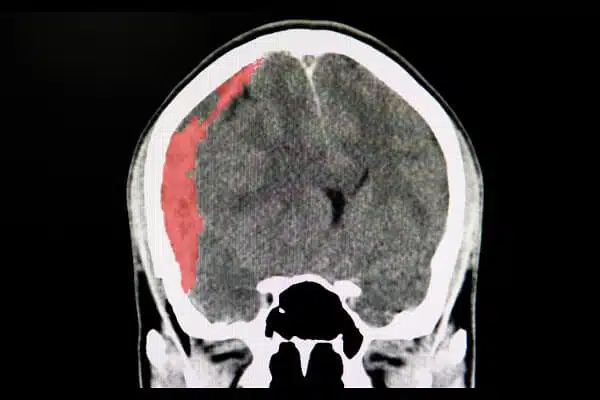

- Hematomas: Blood clots that can put pressure on the brain and may require surgery.

A traumatic brain injury (TBI) can be devastating, impacting every aspect of your life—from daily tasks to your long-term financial security. Whether it’s a mild concussion with persistent symptoms or a severe brain injury causing lifelong problems, the ripple effect on you and your family is profound.